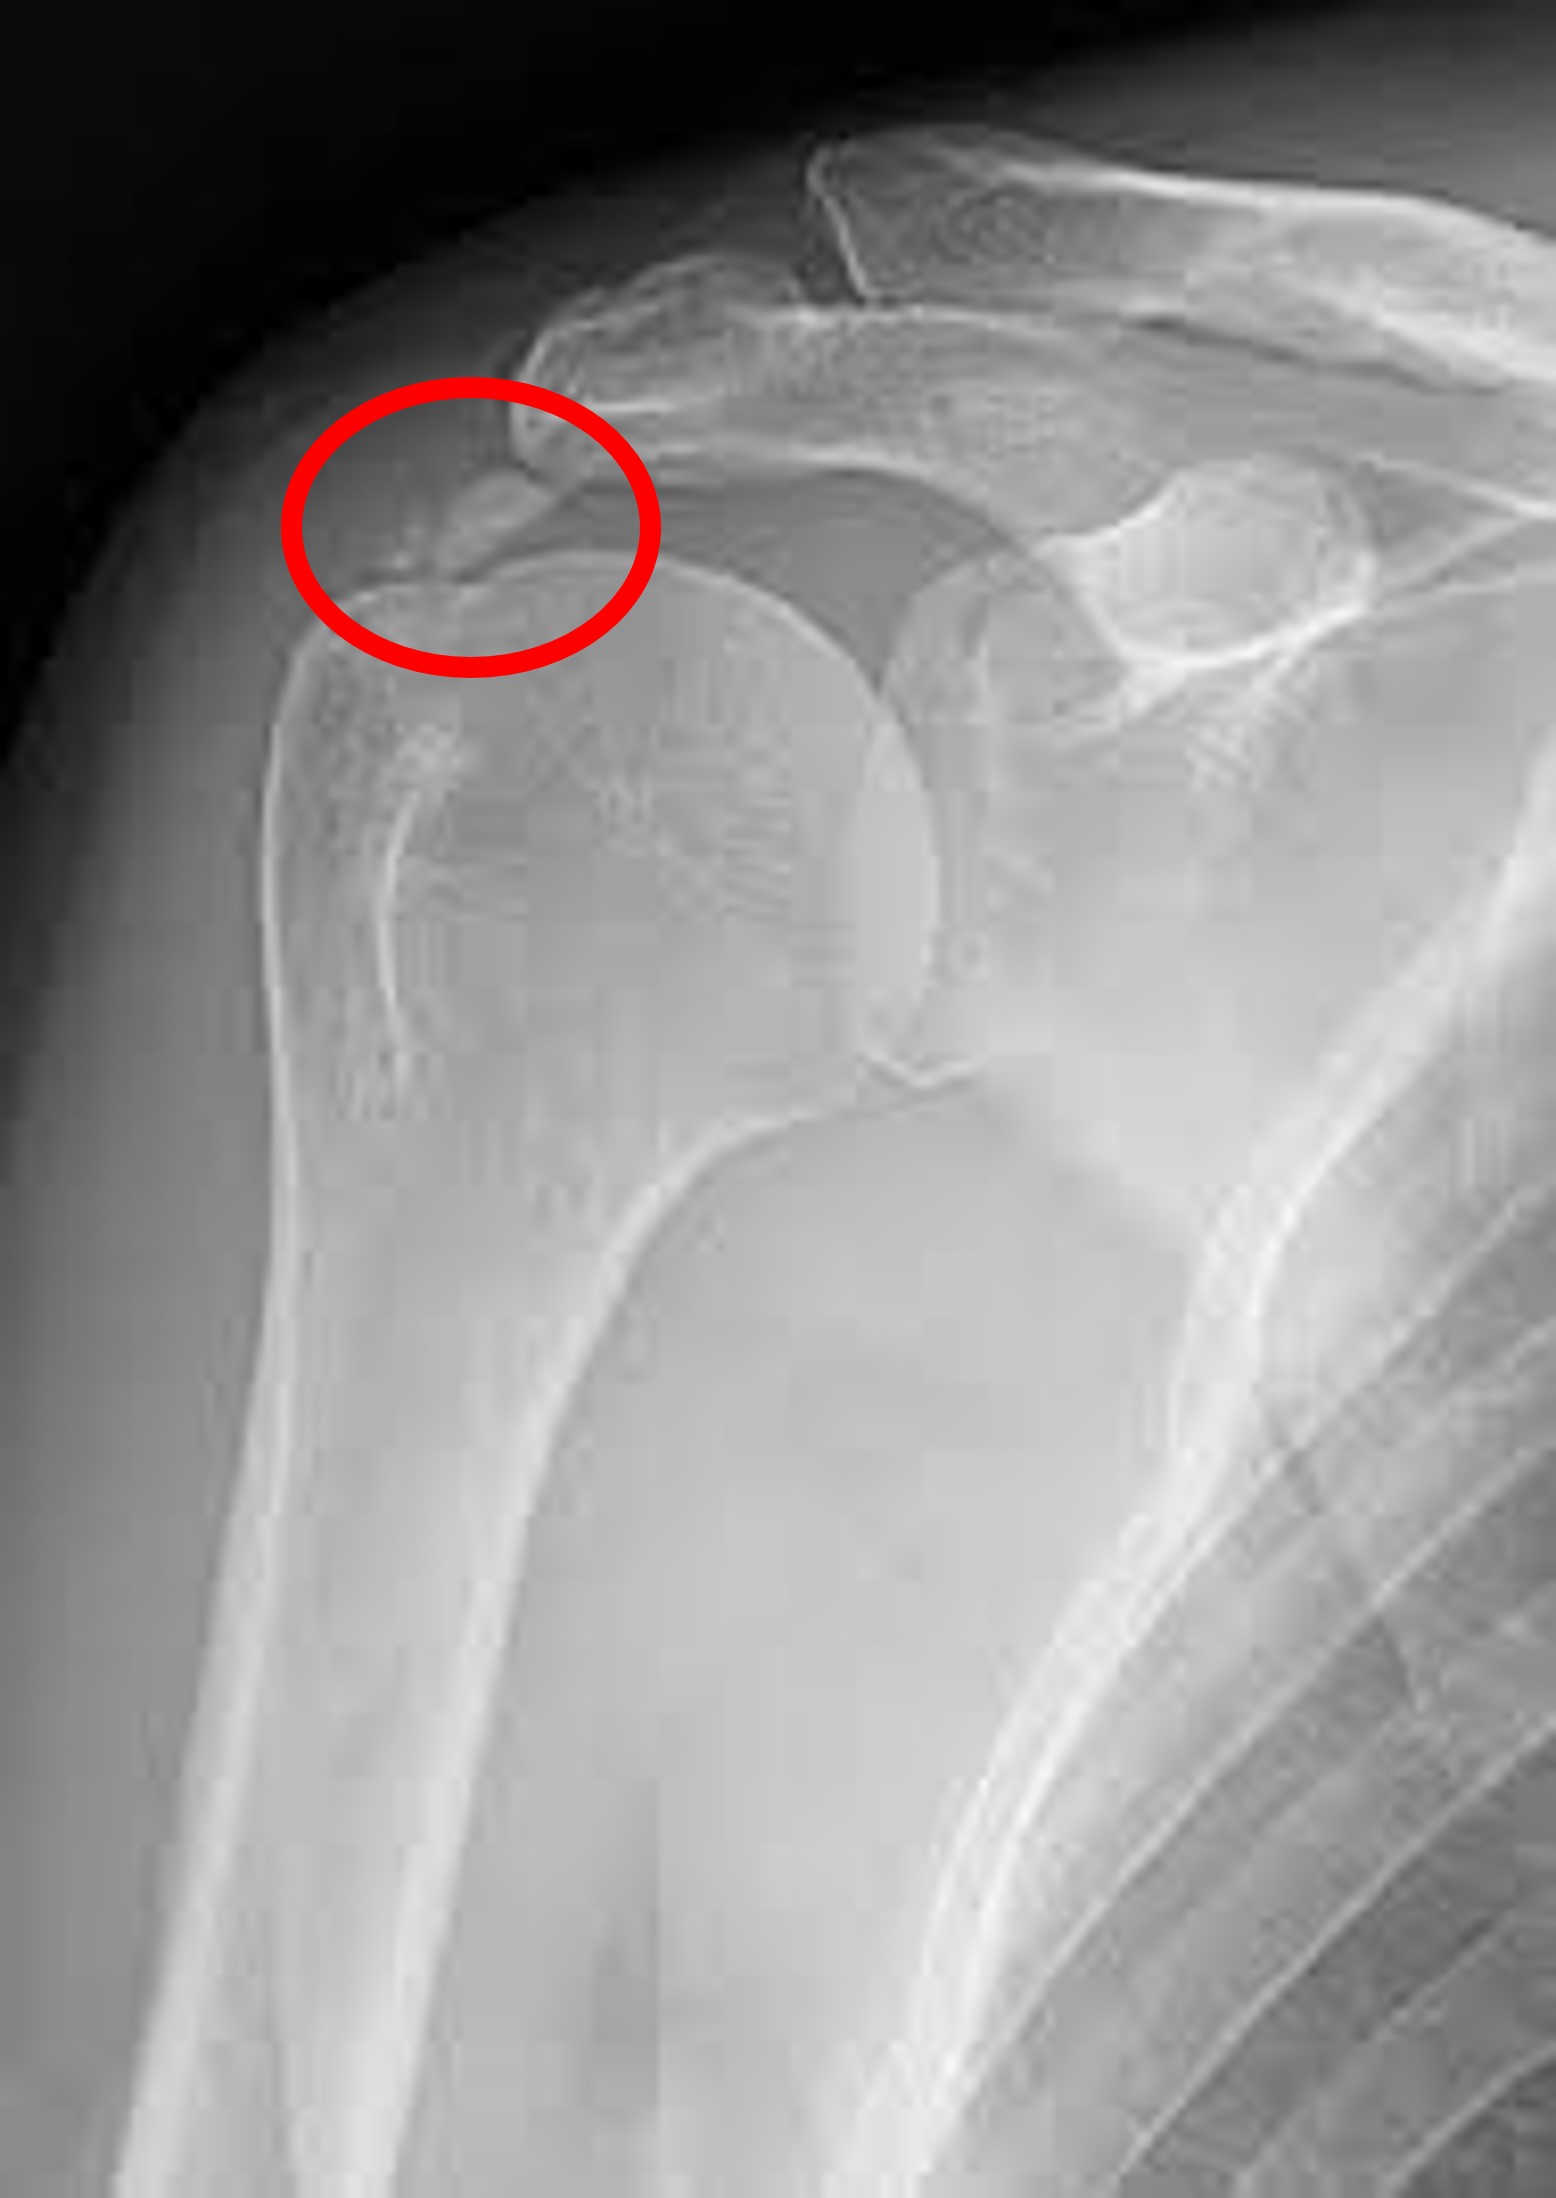

1. X-ray 검사 :

정형외과에 방문하시게되면 가장 많이 하시게 되시는 검사입니다. 가장 기본적이면서도 가장 먼저 감별해야할 위험한 진단을, 예를 들면 골절이나 골종양 등을 발견할 수 있게 해주는 값싸고도 고마운 검사입니다.

회전근개 파열에서 X-ray는 검사의 특성상, 직접적으로 인대를 시각적으로 보여줄 수 없기 때문에, 인대 그 자체에 대한 진단보다는, 인대의 파열을 유발할 수 있는 기저 병변이 있는지를 알아낼 수 있는 장치로써, 기본적으로 촬영하게 되는 검사입니다.

앞에서 말씀드린 회전근개 파열의 내인성 요인 중 하나인 석회가 있는지를 감별하게 해주며, 어깨를 많이 쓰는 직업을 가지신 환자분들의 경우, 극상건과 충돌하는 견봉에 퇴행성 변화중 하나인 '골극'이라는 뾰족하게 솟아오른 골조직을 확인할 수 있습니다. 이 골극이 심한 경우에는 이 골극 자체가 극상건에 손상을 가속하게 되므로, 회전근개 파열을 강력하게 의심할 수 있으며, 추후 수술 시에 단순하게 파열된 회전근개만을 봉합하는 것이 아니라, 추후 재 파열을 일으킬 수 있는 골극을 제거하기 위해서 계획을 짜는데 중요한 역할을 하게 됩니다.